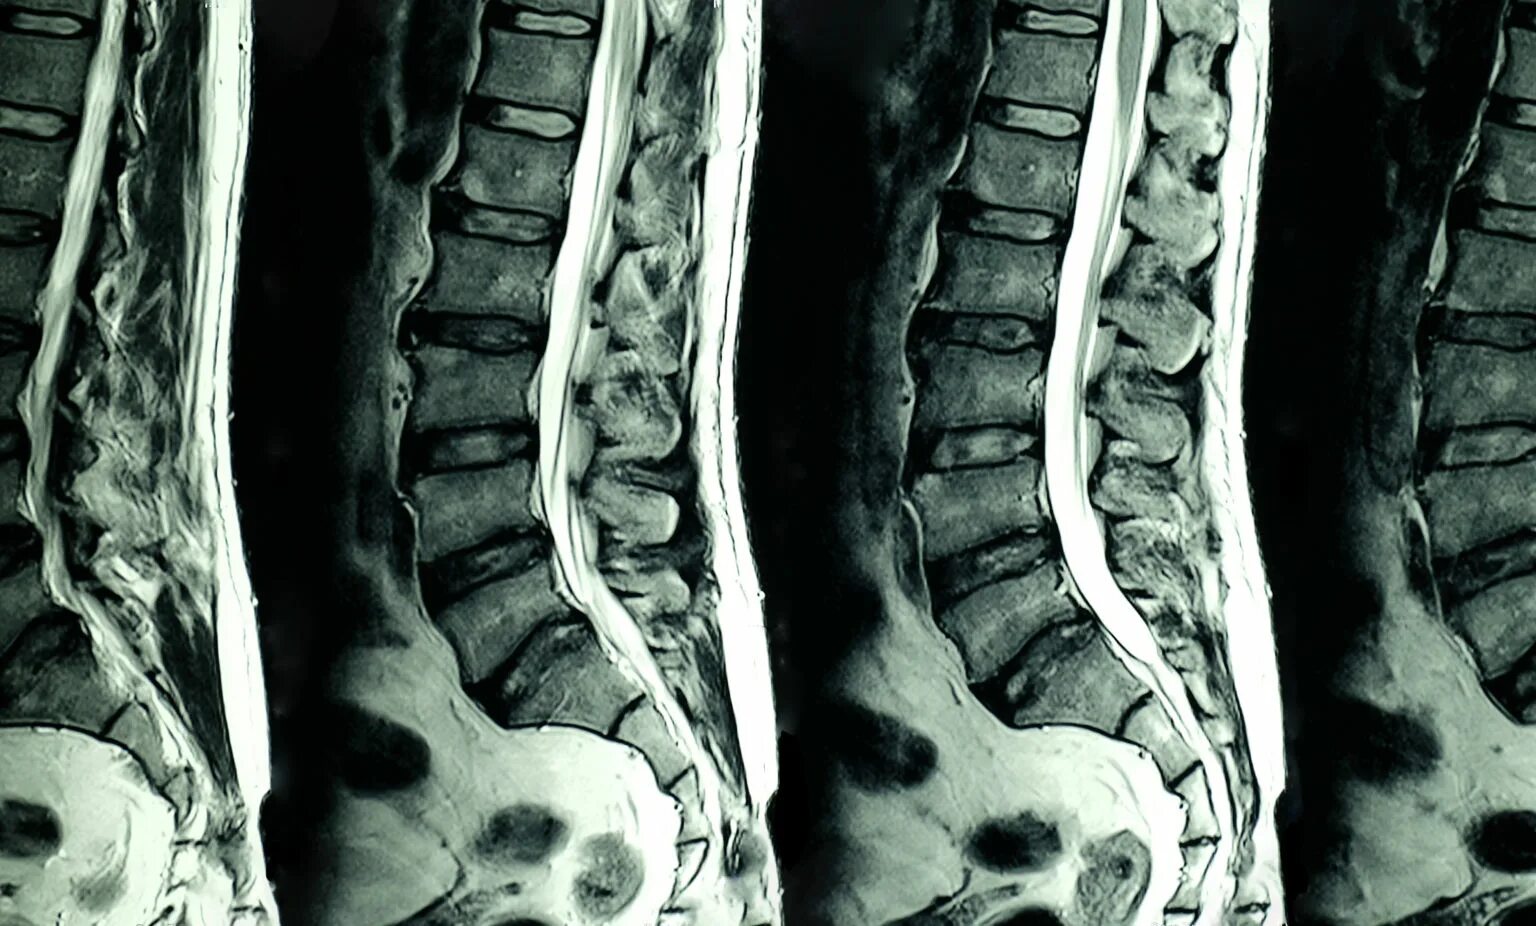

Мрт пояснично крестцового отдела тазобедренные суставы